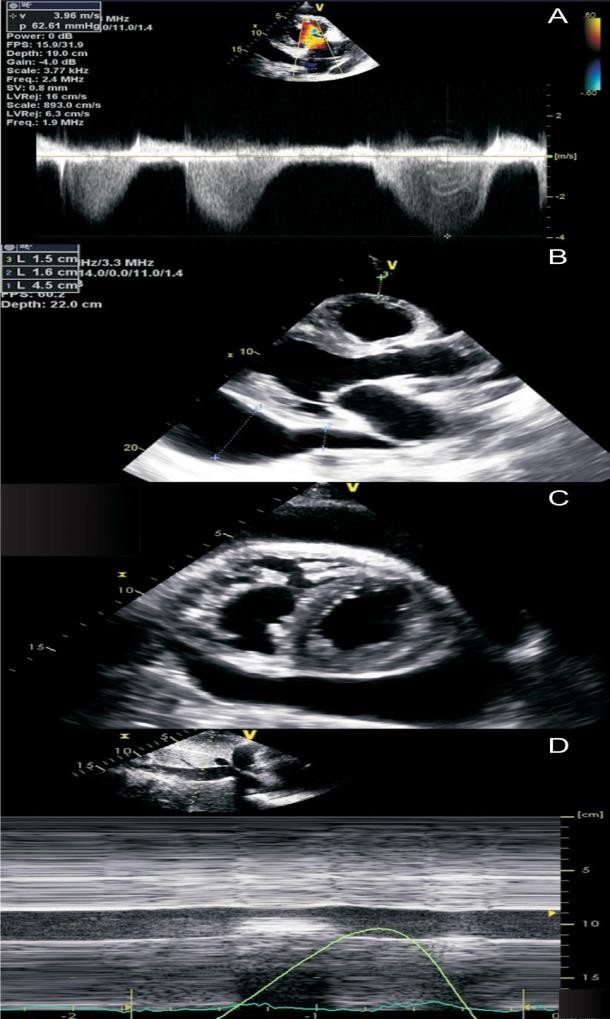

При проведении ЭхоКГ могут быть выявлены ранние признаки констриктивного перикардита, такие как парадоксальное диастолическое движение межжелудочковой перегородки (МЖП) (Приложение А3, рис. 2) [83].

При констриктивном перикардите имеется значительная зависимость профиля кровотока через митральный и трикуспидальный клапаны от фаз дыхания:

по данным импульсно-волновой допплерографии, в начале вдоха максимальная скорость трансмитрального пика E уменьшается на ≥25%;

в начале выдоха максимальная скорость транстрикуспидального пика E уменьшается на ≥40% (Приложение А3, рис. 2) [116].

В диагностике констриктивного перикардита также может быть полезна тканевая допплерография, демонстрирующая так называемый феномен “annulus reversus”, заключающийся в том, что нормальная или повышенная ранняя диастолическая скорость движения медиальной части митрального кольца (медиальная е') оказывается выше, чем ранняя диастолическая скорость движения латеральной части фиброзного кольца (латеральная е’) (Приложение А3, рис. 3) [117].

Сочетание разнонаправленного смещения МЖП в зависимости от фаз дыхания с увеличением ранней диастолической скорости движения медиальной части митрального кольца (медиальная е') ≥9 см/сек имеет самую высокую диагностическую чувствительность (87%) и специфичность (91%) [118].

Парадоксальное движение межжелудочковой перегородки во время ранней диастолы является характерным для пациентов с констриктивным перикардитом. Во время вдоха движение происходит в сторону левого желудочка, во время выдоха — в противоположном направлении [3]. При М-модальном исследовании это проявляется выемкой в раннюю диастолу при определении движения межжелудочковой перегородки, что напоминает нарушения сокращения-расслабления миокарда, наблюдаемые при блокаде левой ножки пучка Гиса или электростимуляции правого желудочка (Приложение А3, рис. 5). При определении этого признака двухмерной ЭхоКГ чувствительность составляет 62%, а специфичность — 93% [3]. Использование допплеровской визуализации тканей можно существенно увеличить чувствительность метода до 82,5% [122].

Допплер-ЭхоКГ позволяет определить парадокс кольца. Он заключается в том, что при относительном сохранении способности миокарда растягиваться в продольном направлении деформация продольной оси левого желудочка и продольная ранняя диастолическая скорость либо нормальные, либо, по мере прогрессирования констриктивного перикардита, увеличиваются. В то время как при рестриктивной кардиомиопатии или при заболеваниях миокарда происходит снижение этих показателей. При этом усредненная максимальная тканевая скорость раннего диастолического смещения септальной части митрального кольца выше латеральной (Приложение А3, рис. 6) [117, 123, 124–128]. Несмотря на высокую чувствительность и специфичность (95% и 96% соответственно), ограничение данного признака при диагностике будет проявляться в случае неоднородности поражения перикарда или при кальцификации кольца митрального клапана.

Характерно динамическое изменение атриовентрикулярного кровотока в зависимости от фазы дыхания (Приложение А3, рис. 7), что отличает констриктивный перикардит от рестриктивной кардиомиопатии. На вдохе пиковая скорость крови уменьшается, а время изометрического расслабления желудочков увеличивается. На выдохе — атриовентрикулярный кровоток возвращается к нормальным значениям. Как правило, прирост пиковой скорости составляет ≥25% на вдохе по сравнению с выдохом [129]. Этот признак обладает 85% чувствительности и 90% специфичности [118].

Застой по большому кругу проявляется отсутствием коллабирования полых и печеночных вен. Особенностью является выявляемый при допплер-ЭхоКГ обратный кровоток, усиливающийся на выдохе больше чем на вдохе (Приложение А3, рис. 8) [132]. В отличие от констриктивного перикардита для рестриктивной кардиомиопатии характерно обратное соотношение.